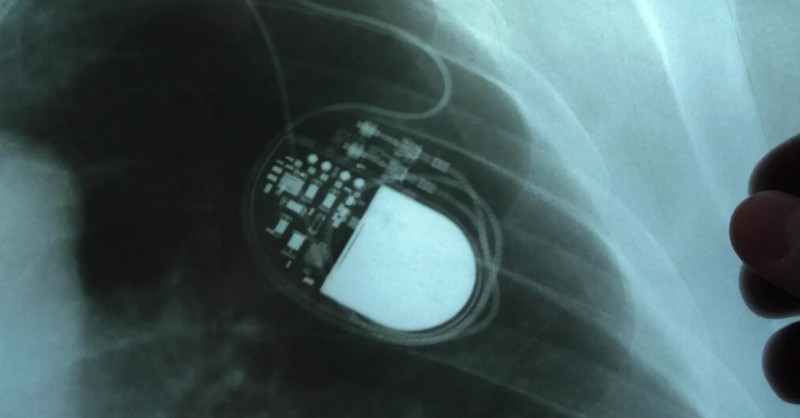

Ministerstvo zdravotnictví podalo trestní oznámení na Fakultní nemocnici Olomouc kvůli podezření z obcházení indikačních kritérií při implantaci kardioverterů-defibrilátorů, což může vést k podvodu a těžkému ublížení na zdraví stovek pacientů. #zdravotnictví #defibrilátory #vyšetřování

Ministerstvo zdravotnictví (MZd) podalo trestní oznámení kvůli operacím pacientů s přístroji na kontrolu srdečního rytmu, takzvaných kardioverterů-defibrilátorů, ve Fakultní nemocnici Olomouc (FNO).

Ministerstvo zdravotnictví podalo trestní oznámení kvůli podezřelým operacím s implantacemi kardioverterů-defibrilátorů ve Fakultní nemocnici Olomouc, což vyvolalo policejní vyšetřování zaměřené na možné obcházení indikačních kritérií a těžké ublížení na zdraví stovek pacientů. #Zdravotnictví #TrestníOznámení #Defibrilátory

Ministerstvo zdravotnictví podalo trestní oznámení kvůli závažným podezřením na manipulaci s dokumentací a obcházení kritérií při implantacích defibrilátorů ve Fakultní nemocnici Olomouc, na což jako první upozornily Seznam Zprávy v loňském prosinci. #zdravotnictví #defibrilátory #bezpečnostpacientů

Ministerstvo zdravotnictví označilo situaci s implantacemi defibrilátorů ve Fakultní nemocnci Olomouc za velmi závažnou a podalo trestní oznámení.

Ministerstvo zdravotnictví podalo trestní oznámení v souvislosti s kauzou defibrilátorů na I. interní klinice Fakultní nemocnice Olomouc, kde interní dokumenty naznačují možné obcházení indikačních kritérií a manipulaci se zdravotnickou dokumentací, a to na základě závažných podezření o neoprávněném čerpání prostředků z veřejného zdravotního pojištění. #zdravotnictví #defibrilátory #trestníoznámení

Ministerstvo zdravotnictví v úterý podalo v kauze defibrilátorů trestní oznámení. Interní dokumenty a datové podklady, které zajistilo, ukazují podle ministerstva na neobvykle vysoké objemy vykazované invazivní péče na I.

Interní audit ve Fakultní nemocnici Olomouc odhalil závažné nesrovnalosti v dokumentaci pacientů zapojených do mezinárodní studie zaměřené na defibrilátory, kdy pouze u dvou z přibližně 70 pacientů byla shoda mezi studijními údaji a nemocničním systémem, a případ nyní vyšetřuje policie pro podezření z podvodu a těžkého ublížení na zdraví. #zdravotnictví #audity #defibrilátory

Loňská interní prověrka v olomoucké fakultní nemocnici odhalila rozsáhlé úpravy dokumentace lidí zařazených do mezinárodní studie o defibrilátorech.

FN Olomouc reaguje na kauzu defibrilátorů: Pacientům nabízí rychlé kontroly

Fakultní nemocnice (FN) Olomouc zprovoznila ve čtvrtek informační linku, na které pacienti s defibrilátorem ICD získají informace o tomto přístroji a mohou se objednat ke kontrole v ambulanci.

"Je to děsivé," okomentoval Novinkami oslovený kardiolog podezření, že na 1. interní klinice- kardiologické Fakultní nemocnice v Olomouci (FNOL) byly v minulosti implantovány defibrilátory ICD i pacientům, kteří je nepotřebovali.

FN Olomouc odmítla tvrzeni policie, že defibrilátory mohly poškodit

Vedení Fakultní nemocnice Olomouc dnes s odkazem na výsledky kontroly odborníků znovu odmítlo tvrzení policie, že implantované defibrilátory ICD mohly některým pacientům se srdečními problémy ublížit.

Olomoučtí kriminalisté zahájili trestní řízení pro podezření z těžkého ublížení na zdraví kvůli implantacím defibrilátorů v FN Olomouc.

Kriminalisté zahájili trestní řízení kvůli podezření z těžkého ublížení na zdraví kvůli implantacím defibrilátorů ve Fakultní nemocnici Olomouc, které nebyly potřebné nebo doporučené.